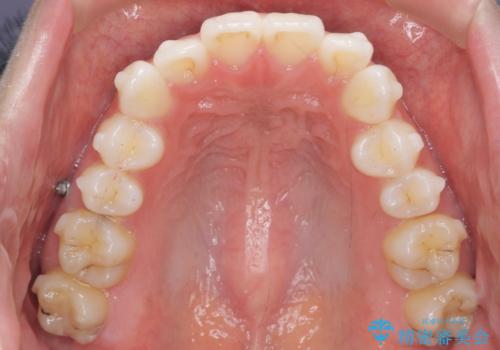

歯を抜かずに後方移動で達成する、前突感の改善

- 前歯が出っ歯のように見えることの改善を求めて来院されました。

当初、セラミックによる治療をご希望されていましたが、相談の結果矯正治療を選択されることとなりました。

通常口元の突出感の改善を行うには小臼歯の4本抜歯が検討されますが、歯のガタ付きが下顎前歯に限定していることから

下顎前歯を1本だけ抜去を行い、上顎の歯は可及的にマイクロインプラントを用いた後方移動を行い口元の印象の改善を計画することとなりました。

マイクロインプラントを用いてしっかりと後方移動を行ったことで前歯の角度は改善され、口元もすっきりと仕上げることができました。